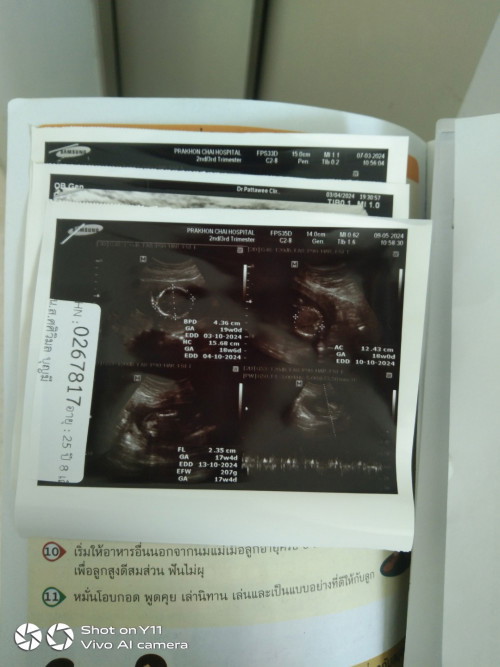

ต้าวจิ๋ว ตอน 15 wk ตอนนี้ 16 wk แล้ว รอลุ้นว่าจะได้ต้าวจิ๋วสาวหรือหนุ่มค่ะ ❤️😘